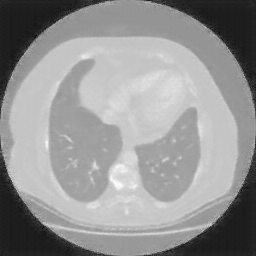

Original NATIVE CT scan (input)

No window - Raw intensity values

Lung window (WL -600, WW 1500 β†’ Low βˆ’1350, High +150)

Mediastinum window (WL 40, WW 400 β†’ Low βˆ’160, High +240)